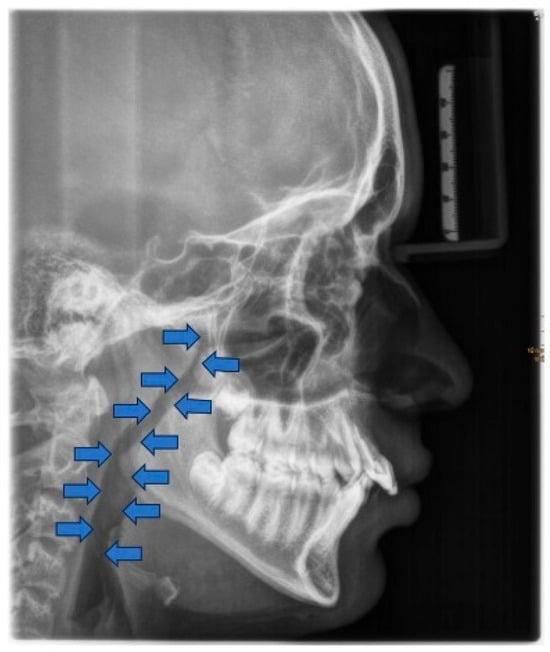

Cephalometric evaluation of patients with OSA has revealed several skeletal (a) and soft tissue (b) morphological alterations compared to normative values [81,82] (Table 1).

The consequences of these anatomical alterations result in a reduced size of the bony nasopharynx and a hyperdivergent facial pattern, characterized by increased anterior facial height. A bimaxillary retrognathic pattern, more pronounced in the mandible than the maxilla, and a decreased facial depth further contribute to a narrowed posterior airway space [83]. Together, these structural changes significantly reduce upper airway volume, thereby predisposing affected individuals to OSA (Figure 3).